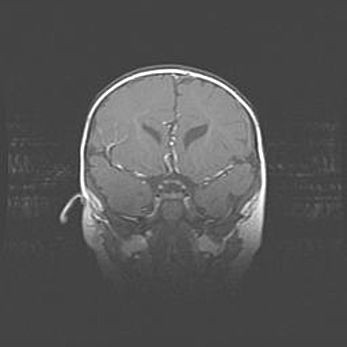

Множественные кисты обоих полушарий головного мозга, наибольшая из них в правой затылочной области. Ассиметричная атрофическая гидроцефалия.

Возраст: 7 месяцев

Вес: 5660 г

Пол: мужской

Окружность головы: 41,5 см

Срок гестации: 28-29 недель

Кисты головного мозга развиваются в результате многоочаговых некрозов вещества мозга и возникают вследствие перенесенной перинатальной инфекции, менингитов, энцефалитов, асфиксии, родовой травмы, расстройств мозгового кровообращения различного генеза. Образованию кист в веществе головного мозга плодов и новорожденных способствуют такие факторы, как высокое содержание в нем воды, недостаточная (или отсутствие) миелинизация и слабая астроглиальная реакция на повреждение.

Кисты могут сочетаться с гидроцефалией и другими поражениями головного мозга.